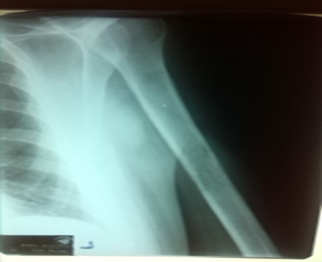

In the following days, the patient's general condition suddenly worsened, with pronounced weakness and malaise along with constant high fever. The patient complained of pain throughout the body, especially severe pain in the left upper arm with the inability to move the arm and assume a forced position. An X-ray of the left upper arm was performed/ Picture2/. and an orthopedist was consulted. Dg. Meta humeri sin. Th: bisphosphonates were recommended.

Picture 2